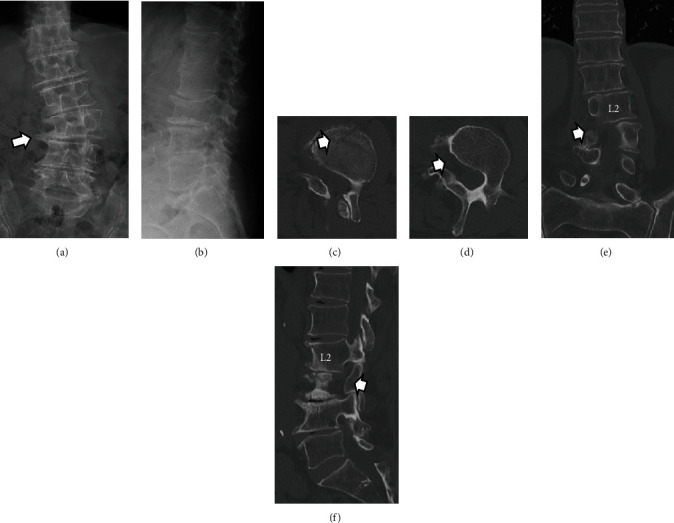

Background: Patients with congenital absence of a lumbar pedicle and nerve root anomaly presenting with ipsilateral foraminal stenosis are extremely rare. Case Presentation: An 80-year-old man had low back and right thigh pain. Radiographs and computed tomography (CT) showed L3 vertebral body fracture and the absence of the right L3 lumbar pedicle. He was diagnosed with L2-L3 right foraminal stenosis caused by an L3 vertebral fracture and underwent lumbar fusion at L2-L3 and L3-L4. Intraoperatively, we confirmed that an anomalous nerve root was divided from the right L2 nerve root near the dorsal root ganglion (DRG). Conclusions: Patients with congenital absence of a lumbar pedicle are less prone to ipsilateral foraminal stenosis because they theoretically have a large space in the foramen. This rare case was caused because of additional instability due to vertebral fracture under the condition of a nerve root anomaly and lumbar degeneration.